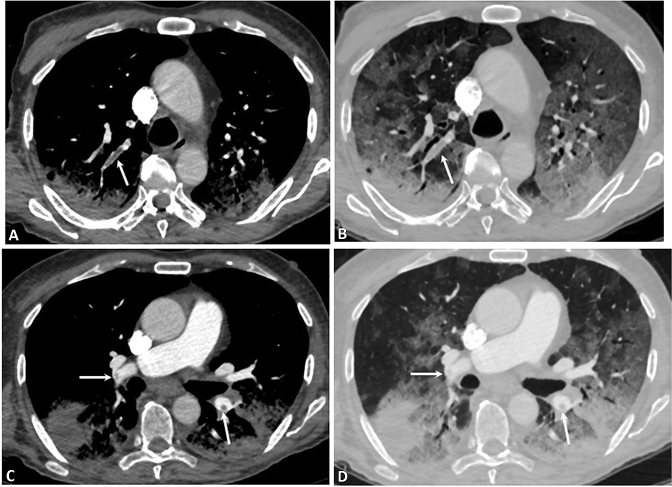

Fig. 2.

CTPA images on the axial planes—CT-staging system Stage 3. a window width and level for the evaluation of mediastinum allow us to correctly evaluate the presence of clot (arrows) inside the lobar branch for the right upper lobe. b window width and level for the evaluation of lung parenchyma allow us to correctly evaluate the presence of diffuse and confluent GGOs with air bronchogram associated. c window width and level for the evaluation of mediastinum allow us to correctly evaluate the presence of small clot (arrow) inside the lobar branch of RPA. d window width and level for the evaluation of lung parenchyma allow us to correctly evaluate the presence of diffuse and confluent GGOs with air bronchogram associated. Moreover, it is possible to appreciate the presence of bilateral consolidations, with a subpleural distribution